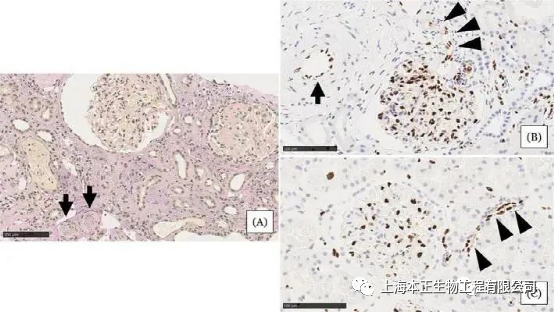

患者移植后1年(D,F)和8年(E,G)肾活检显示患者具有免疫耐受状态

研究人员认为,本案例成功真正归因于移植前干细胞输注所诱导出持续促耐受性环境。本病例提供了新的证据,证明在活体肾移植中,间充质干细胞可在移植后安全、完全停用维持性抗排斥药物,最终达到免疫耐受状态。